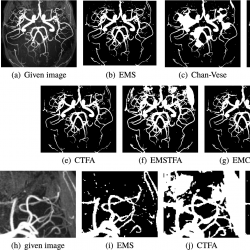

Example 5.

This example is a $512\times 512$ TOF-MRA Circle of willis inverted MIP of carotid vascular system (Fig. 8(a)) from http://www.mr-tip.com. Figures 8(b)–(g) show the results of vessel extraction by EMS, STFA, Chan-Vese, CTFA and the presented methods, respectively. In the presented method we used $\alpha =1$ and $\beta =0.25$ to segment this MRA image.

The extracted vessels by Chan-Vese, STFA and CTFA methods give unsatisfactory results. These methods are unable to recover the vessels of some regions, for example, see the upper right side of Figs. 8(a), (b), (d) and (f) (for better viewing, we enlarged this part in Figs. 8(e)–(h)). EMS method has artifacts near vessel boundaries and other regions, and the presented method removes most of them. This example also shows the ability of the presented method to segment regions of the background so that their intensity is close to the vessel and does not detect them as a vessel inaccurately. As shown in Table 1, in this example, EMCTFA method converges by less iteration than CTFA algorithm too.

infor435_g008.jpg

Fig. 8

Example 5. TOF-MRA Circle of Willis Inverted MIP of carotid vascular system extraction. (a) Given image; (b)–(f) Results by EMS, Chan-Vese, STFA, CTFA and EMSTFA methods, respectively; (g) Results of the presented method; (h)–(k) are the zoomed-in parts of (a), (b), (d) and (e).